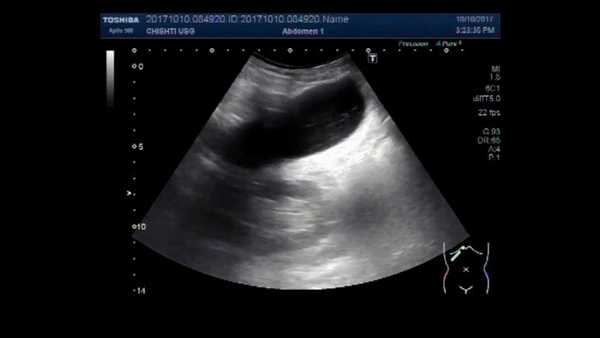

• Абдоминальное УЗИ. Определит структурные изменения железы, участки обызвествления, воспаление и отечность тканей, наличие камней в желчном пузыре.

УЗИ поджелудочной железы

УЗУЗИ поджелудочной железы очень важно при определении острого заболевания, наблюдении за патологией в хронической стадии и контроля состояния поджелудочной при лечении. Данный вид диагностики вы можете выполнить в наших мед. центрах «Здоровье Плюс».

Поджелудочная железа является одним из важных внутренних органов, нарушения в функционировании которого, могут привести к тяжелым заболевания. Одним из самых быстрых, высокоточных и безопасных методов считается УЗИ. Оно помогает выявить патологические и воспалительные процессы, отклонения в развитии органа, наличие новообразований и т.д.

- УЗИ - показывает размер железы, уплотнения, фиброзные участки;

Абдоминальное УЗИ поджелудочной железы внешним датчиком

Исследование осуществляется стандартно, через брюшную стенку, наружным датчиком.

Место осмотра покрывается специальным гелем для максимального контакта датчика с поверхностью кожи, после чего врач медленно перемещает прибор в центральной части живота с постепенным смещением к левому подреберью.